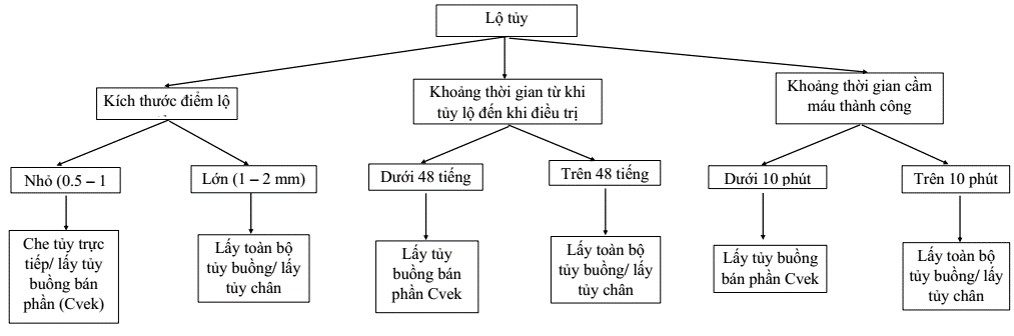

Lộ tủy do cơ học tiên lượng tốt hơn lộ tủy do sâu. Thứ 2 là kích thước điểm lộ tủy, càng nhỏ càng tiên lượng tốt. Thứ 3 là khoảng thời gian từ khi lộ tủy đến khi che tủy, càng lâu thì vi khuẩn càng có cơ hội xâm nhập và gây nhiểm khuẩn buồng tủy.

Các yếu tố sau đây giúp tiên lượng che tủy tốt:

- Lộ tủy do chấn thương hoặc cơ học.

- Cầm máu được trong vòng dưới 10 phút.

- Kích thước điểm lộ tủy < 1 mm.

- Điều trị được thực hiện trong vòng 48 tiếng sau khi tủy lộ.

Điều trị răng lộ tủy được tóm tắt trong sơ đồ sau:

Chỉ định che tủy trực tiếp

– Răng không có triệu chứng như đau tự phát, đau chói, đáp ứng với thử nhiệt, điện, tủy răng bình thường..

– Kích thước điểm lộ tủy < 0.5 mm.

– Cầm máu dễ (< 10 phút).

– Vị trí tủy lộ phải sạch và không bị nhiễm khuẩn (nạo ngà sau khi cách li bằng đê cao su).

– Lộ tủy do chấn thương, lau khô răng không thấy chảy máu ngà (dentin blushing).